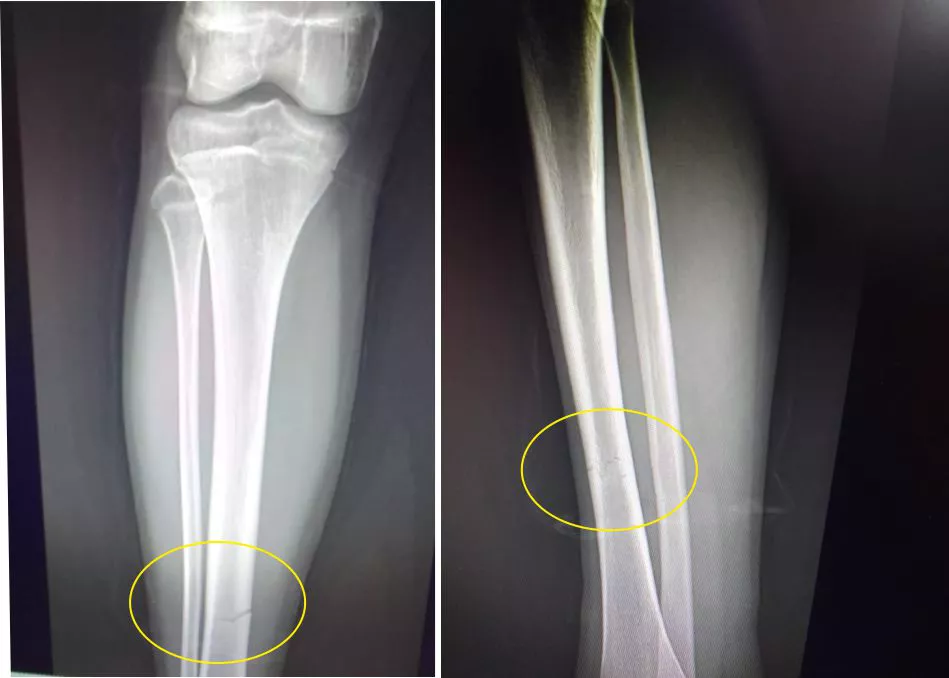

“En Santa Isabel – continuó la madre - el médico me confirma que no era desgarro, que mi hija tenía una fractura de tibia. Le colocan un yeso. Tiene que estar siete días con reposo absoluto”.

La enfermera me dijo que le pusiera hielo, que era un desgarro. El lunes se efectuó la derivación a Santa Isabel y allí el médico me dice que mi hija tiene fractura